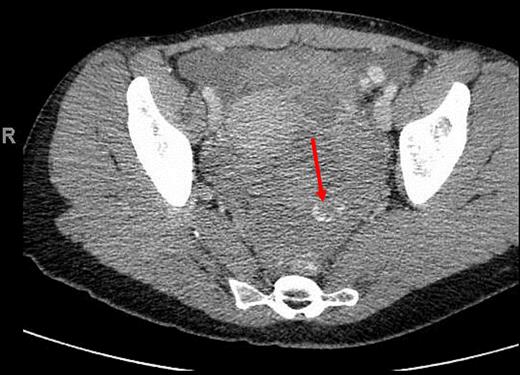

CT (axial view) of the pelvis showing extravasation of contrast material into the left pelvis (red arrow).

A 34-year-old female with no past medical history was transferred to our emergency department from an outside hospital due to concern for intra-abdominal bleeding. She initially presented with lower abdominal pain immediately following vaginal intercourse described as nonvigorous with the patient mostly ‘on top’, and no history of foreign body use or trauma. CT of the abdomen and pelvis with IV contrast performed at the outside hospital revealed an intra-abdominal hematoma with extravasation of contrast questionably from one of the branches of the left internal iliac artery (Figs 1 and 2). No adnexal lesions were identified on the CT. Upon arrival, the patient was complaining of constant, sharp, severe bilateral lower quadrant abdominal pain, nausea and fatigue. There was no history of loss of consciousness, vomiting, vaginal or rectal bleeding, or hematuria. A past surgical history consisted of appendectomy. Her last menstrual period was 19 days prior to presentation.